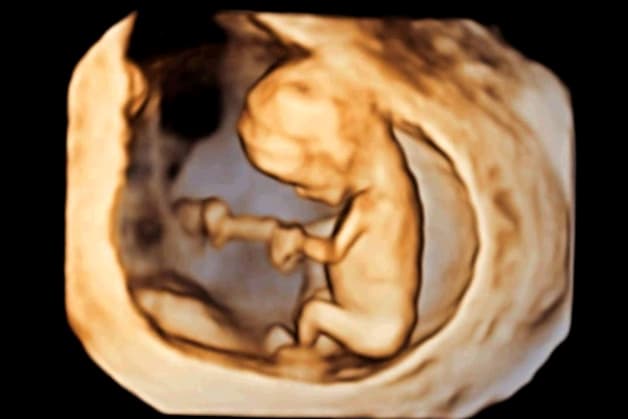

Xét nghiệm dị tật thai nhi là những phương pháp nhằm cung cấp những thông tin về chỉ sổ phát triển của em bé giúp cho bố mẹ biết được rằng thai nhi có mắc phải rối loạn di truyền nào dẫn đến dị tật hay không. Để phát hiện được những dị tật này không chỉ dựa vào quá trình quan sát vẻ bề ngoài thông qua siêu âm. Bởi vì, dị tật không chỉ bao gồm sự khác biệt về hình thái mà còn cả các vấn đề về chức năng.

Xét nghiệm dị tật giúp cho bố mẹ biết được rằng thai nhi có mắc phải rối loạn di truyền nào dẫn đến dị tật hay không